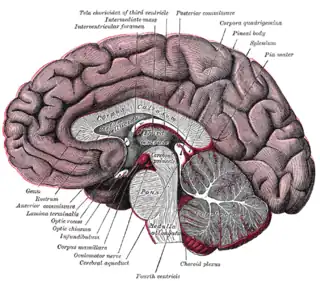

El cuerpo pineal está etiquetado en estas imágenes.

Aspecto mesal de un cerebro seccionado en el plano sagital mediano. Disección que muestra los ventrículos del cerebro.

Disección que muestra los ventrículos del cerebro. Vista anterolateral de las regiones medias y traseras del cerebro.

Vista anterolateral de las regiones medias y traseras del cerebro. Sección sagital mediana del cerebro.

Sección sagital mediana del cerebro. Glándula pineal.